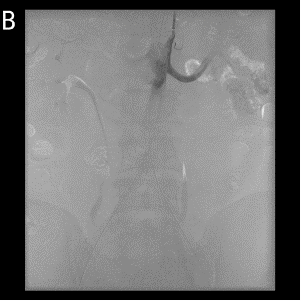

图3介入手术前后动脉造影对比。A)术前造影,见主动脉于肾动脉水平下狭窄,肠系膜下动脉显影,以下闭塞;B)术后造影,见双侧髂动脉通畅。